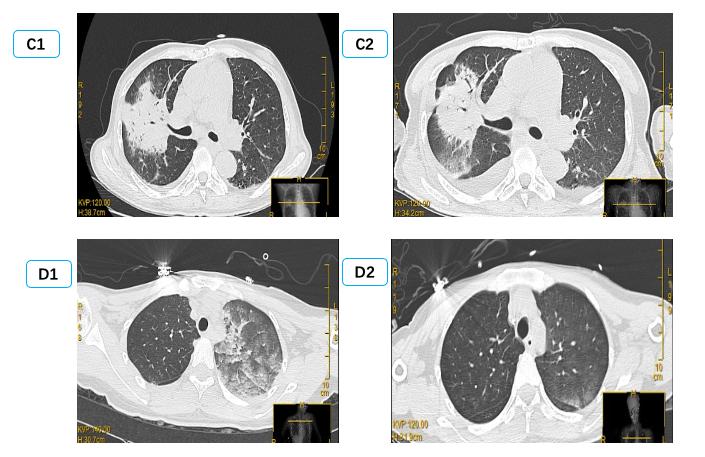

图 4 患者B胸片及肺部超声改变过程 Fig 4 X-ray and lung ultrasound image of patient B

由于单侧PE病情轻重不一,影像表现可以为间质B线、毛玻璃影,严重可表现为肺实变,因此常误诊为肺部感染、肺出血、支气管扩张、肺实变等[29-31]导致病情延误。本研究中有12例单侧PE患者初次影像报告未准确识别; 因此建立重复可量化的单侧PE影像定义及分级标准有组于单侧PE诊断[32]。有心脏病史,心脏超声提示长期二尖瓣反流,长期有右侧胸腔积液,结合入院后床边BNP及肺部超声可以进行鉴别,尤其是床边重症超声可以及时发现明显二尖瓣反流,及时监测肺部超声表现可予以鉴别诊断。如图 4中B患者,入院前肺部CT正常,因失血性休克导致心脏骤停3 h后胸片提示右侧渗出加重,肺部超声由A线为主逐渐发展为B7线、B3线、融合B线及肺实变,提示患者PE程度逐渐加重; 同时心脏超声提示新发重度二尖瓣反流,综合考虑诊断单侧PE,经呼吸支持,利尿治疗后患者胸片、肺部超声均迅速恢复正常。而长期心衰合并二尖瓣反流患者,联合下腔静脉、颈静脉等超声进行容量评估,可与肺部感染相鉴别[33]。急性胸痛患者肌酸激酶同工酶联合床边及时检测肌钙蛋白,可早期诊断心肌梗死,为诊断心源性PE提供依据,本研究中两组间心肌损伤标志物差异无统计学意义。